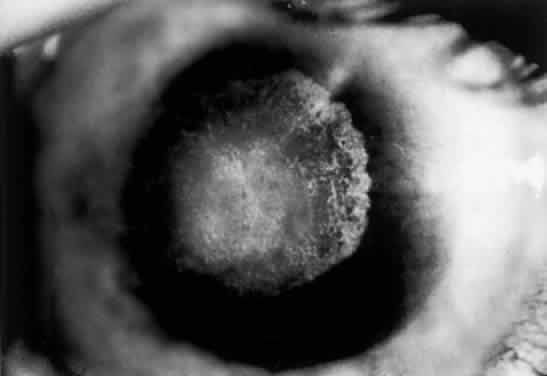

OCULAR FINDINGS. The outstanding clinical feature common to all three phenotypes is the corneal and conjunctival cystine crystal deposition (Figs. 3 and 4). Photophobia is often the only presenting visual symptom; this may be incapacitating and associated with blepharospasm.

Fig. 3. Cystinosis. Refractile crystals noted throughout the corneal stroma.

Corneal deposits appear as a layer of homogeneously distributed, fusiform or needle-shaped, iridescent crystals situated in the stroma beneath the epithelium. In the infantile form, anterior crystal deposition begins early in life (between 6 and 15 months of age) and proceeds posteriorly as the patient ages; deposition advances more rapidly in the periphery. The anterior location of the crystals may be associated with recurrent erosions.33 The depth of the stromal deposition and the density of crystals is always greater peripherally than centrally. More and larger crystals occur in the superficial stroma. No visual impairment occurs at this early stage. By the age of 7 years, most patients have crystals, either within or on the endothelial surface34,35; markedly decreased corneal sensitivity is also present.36 The spherical contrast sensitivity function is significantly lower in infantile cystinosis than in age-matched controls.37

The conjunctiva has a ground-glass appearance. Polychromatic, polymorphic, rectangular, or rhomboidal crystals can be seen with the biomicroscope.